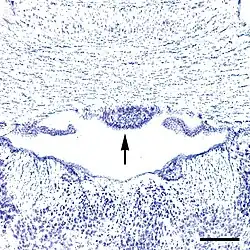

As noted above, capillaries in some subregions within the SFO are fenestrated,[6] and thus lack a blood–brain barrier. All circumventricular organs except the subcommissural organ contain fenestrated capillaries,[2] a feature that distinguishes them from most other parts of the brain.[7] The SFO can be divided into six anatomical zones based on its capillary topography: two zones in the coronal plane and four zones in the sagittal plane.[3] The central zone is composed of the glial cells, neuronal cell bodies and a high density of fenestrated capillaries.[8] Conversely, the rostral and caudal areas have a lower density of capillaries[8] and are mostly made of nerve fibers, with fewer neurons and glial cells seen in this area. Functionally, however, the SFO may be viewed in two portions, the dorsolateral peripheral division, and the ventromedial core segment.[9]